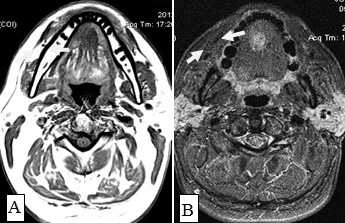

С помощью КТ сложно было выявлять опухоли малых размеров (Т1стадия) и их границы в результате низкой контрастности, а также новообразования с поверхностным распространением (рис. 1). Вместе с тем, 72,0% обследованных больных имели Т3, Т4 стадии опухолевого процесса и после болюсного введения контрастного вещества контрастность опухоли повышалась. С увеличением размера опухоли отмечалась неоднородность усиления из-за наличия некроза (рис. 2). Жировые пространства подъязычной области в нормальном состоянии представляют собой симметричную зону низкой плотности между челюстно-подъязычной и подбородочно-подъязычной мышцами. Облитерация жировых пространств подъязычной области служила основным показателем опухолевого поражения при выявлении небольших образований дна полости рта (рис. 3,4).

Рис.1. Пациент Ж., 58 лет. МСКТ ротоглотки в аксиальной проекции: А - нативное исследование, В - с внутривенным болюсным контрастированием. Небольшая инфильтративная опухоль ротоглотки (левой небной миндалины Т1 стадии). Границы опухоли не дифференцируются, накопление контраста слабое (показатели плотности в нативной фазе исследования 45 ед.Н, после внутривенного болюсного усиления - 56 ед.Н). Определяется смещение левой стенки ротоглотки, сглаженность контура (стрелки)

Не возникало сложностей в выявлении опухолевых узлов Т3, Т4 стадий, имевших все отмеченные выше признаки в различных сочетаниях в 36 исследованиях (рис. 11). Из 50 обследованных с помощью МСКТ и МРТ пациентов у 26 (52,0%) были выявлены метастазы в лимфатических узлах шеи. Поражались преимущественно лимфатические узлы I-II уровня. Признаками метастаза плоскоклеточного рака в лимфатических узлах были: увеличение размера лимфатического узла более 1,0 см, изменение формы лимфатического узла с бобовидной на округлую, структурные нарушения в узле, нечеткость наружных контуров узла, уплотнение окружающей жировой ткани на КТ или изменение сигнала на МРТ.

Большинство пораженных метастазами лимфатических узлов имели размеры более 1,0 см, округлую форму (рис. 12). Внутривенное контрастирование при оценке изменений в лимфатическом узле являлось обязательным условием для уточнения внутренней структуры и выявления зон некроза. В результате гипоксии и распада ткани формируется центральная зона некроза, не накапливающая контрастный препарат при внутривенном болюсном усилении. При этом отмечается повышение плотности в периферических отделах лимфатического узла (рис. 13).